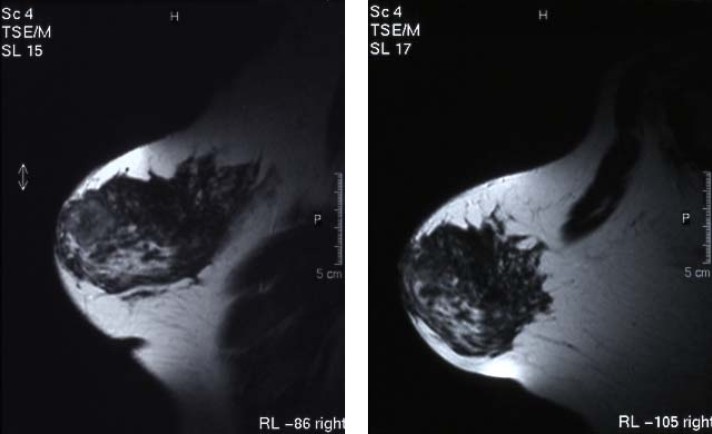

病例4 乳腺癌 stage IIIA

A 治疗前DSA示乳腺病灶 B 微血管介入后立即造影瘤染色消失

C 治疗前DSA D 治疗后3个月见病灶消失